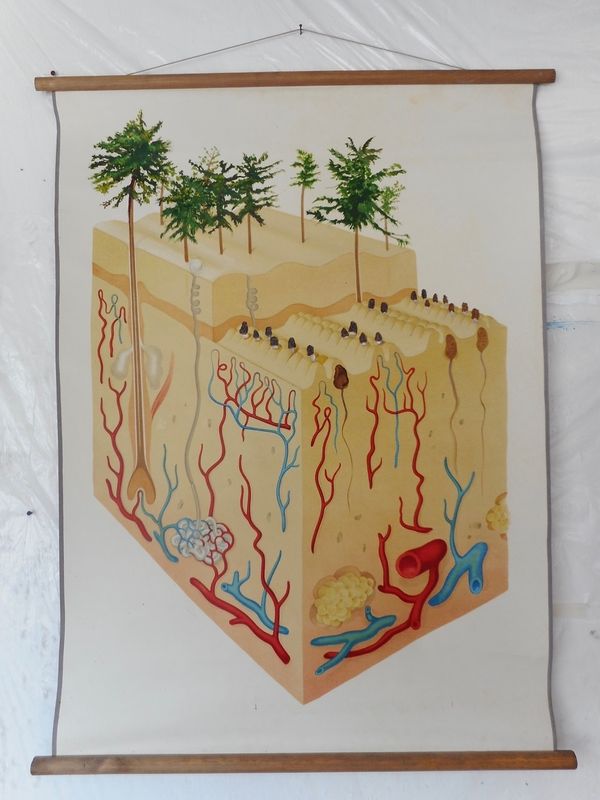

2018 - anatomy (the skin)